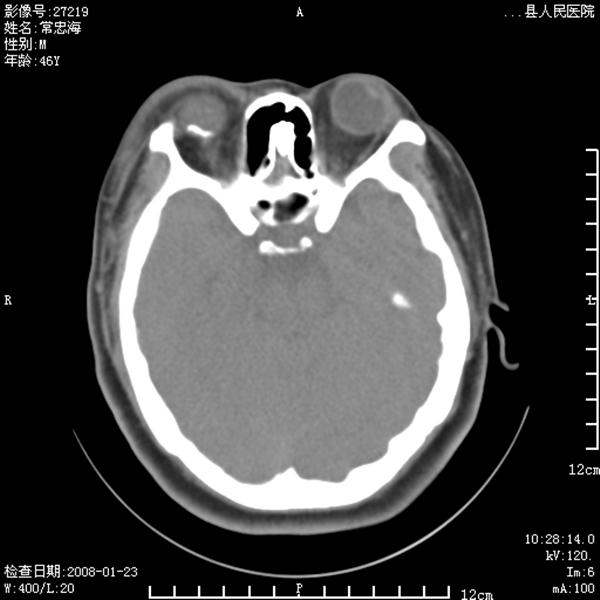

以下是引用江边学者在2008-4-19 22:26:00的发言:[br]1.胼胝体发育不良。[br]2.右侧眼球痨。[br]3.右侧颜面部软组织挫伤。